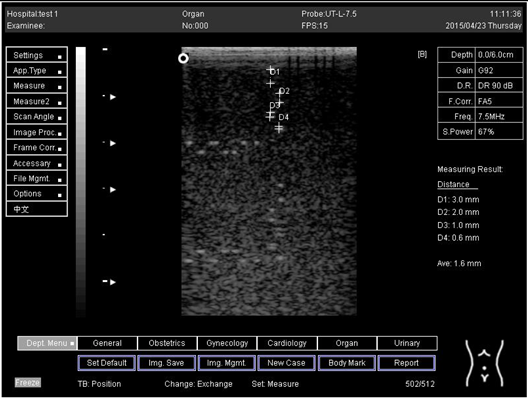

9.0 Axial resolution

Biomimetics 07 00130 i001

D1 = 4.9

D2 = 4.1

D3 = 3.1

D4 = 2.2

Lateral resolution

Biomimetics 07 00130 i002

D1 = 5.0

D2 = 4.0

D3 = 3.0